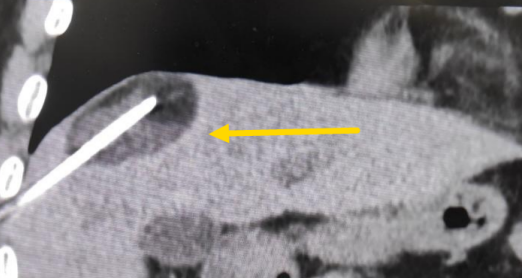

這個(gè)患者病變位置刁鉆,穿刺難度大,冷凍消融的難點(diǎn)在于既要不損傷膈肌和肺組織,同時(shí)又要盡最大可能完全消融腫瘤。術(shù)前陳寶瑩主任、李鐵柱教授、兀云飛醫(yī)生詳細(xì)設(shè)計(jì)進(jìn)針路徑、布針計(jì)劃,術(shù)中微創(chuàng)團(tuán)隊(duì)協(xié)調(diào)配合,李鐵柱教授仔細(xì)操作,精準(zhǔn)到位,順利完成兩個(gè)病變的布針,遂啟動(dòng)治療,先快速降溫到-150多度,再升溫至15?,經(jīng)過(guò)兩個(gè)循環(huán)反復(fù),即刻觀察到病變完全被冰球覆蓋,同時(shí)周圍臟器無(wú)損傷,術(shù)中患者幾乎沒(méi)有疼痛,還和醫(yī)生聊起了天。

術(shù)中冰球形成